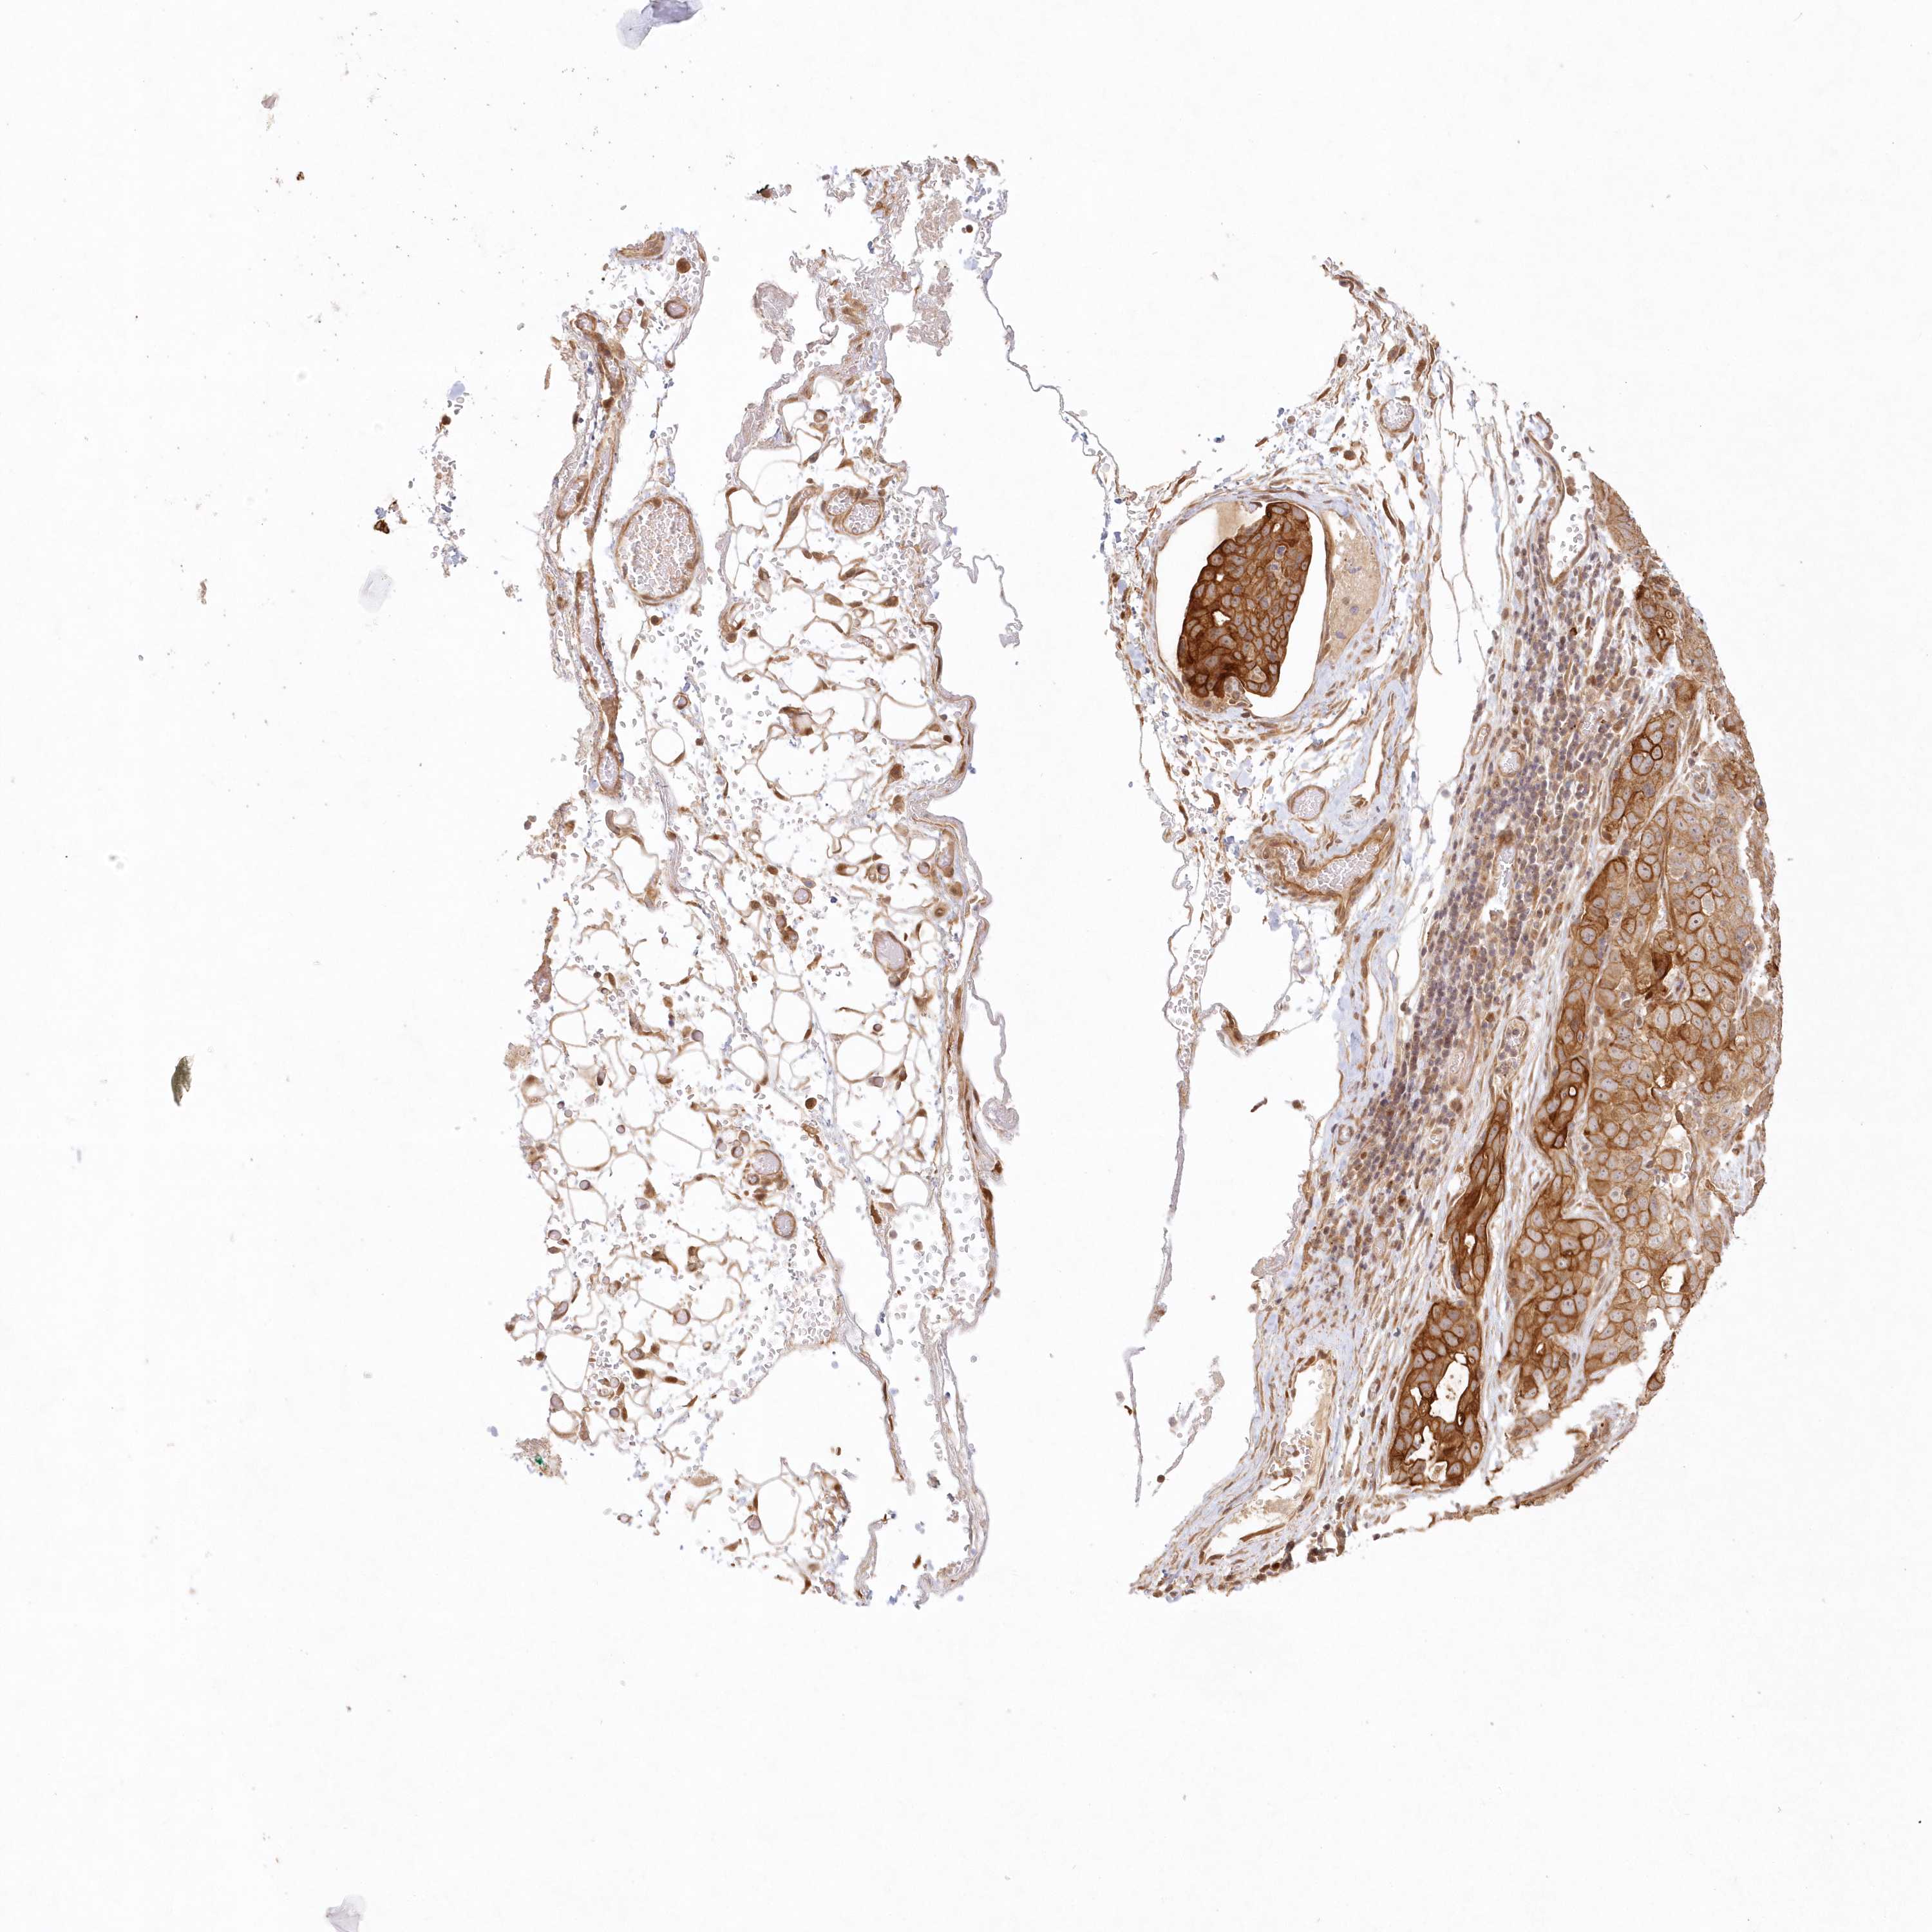

STOMACH CANCER - Protein expressioni

A mouse-over function shows sample information and annotation data. Click on an image to view it in a full screen mode. Samples can be filtered based on level of antibody staining by selecting one or several of the following categories: high, medium, low and not detected. The assay and annotation is described here.

Note that samples used for immunohistochemistry by the Human Protein Atlas do not correspond to samples in the TCGA dataset.

Antibody stainingi

Antibody staining in the annotated cell types in the current human tissue is reported as not detected, low, medium, or high, based on conventional immunohistochemistry profiling in selected tissues. This score is based on the combination of the staining intensity and fraction of stained cells.

Each image is clickable and will lead to virtual microscopy that enables deeper exploration of all samples and also displays staining intensity scores, fraction scores and subcellular localization as well as patient and tissue information for each sample.

Antibody HPA036891

Antibody HPA036892

Antibody HPA061498

Staining

High

Medium

Low

Not detected

Intensity

Strong

Moderate

Weak

Negative

Quantity

>75%

75%-25%

<25%

None

Location

Nuclear

Cytoplasmic/membranous

Cytoplasmic/membranous,nuclear

Adenocarcinoma, NOS